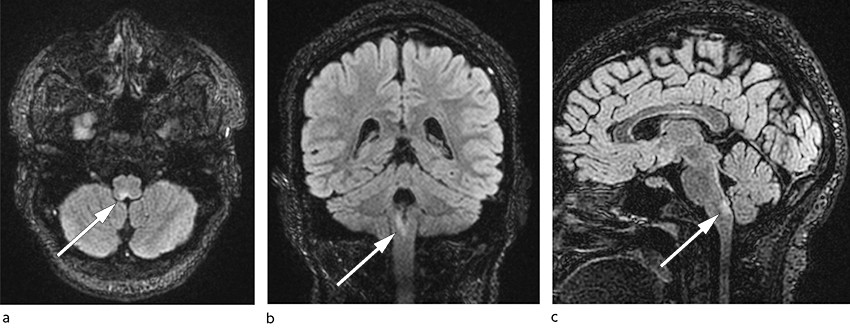

Fire dager etter utskriving ble kvinnen reinnlagt grunnet forverring av plagene. De første to dagene etter utreise klarte hun å få i seg noe mat og drikke, men deretter fikk hun igjen akutt kvalme og oppkast rett etter matinntak. Kliniske biokjemiske analyser var i hovedsak uendrete eller normaliserte sammenlignet med ved første gangs innleggelse: natrium 141 mmol/L, kalium 3,9 mmol/L og lett trombocytose 452 × 109/L, men ellers normale verdier, blant annet CRP < 1 mg/L, Hb 14,0 g/dL, leukocytter 7,7 × 109/L, ALAT 34 U/L, ALP 71 U/L og bilirubin 6 µmol/L. 30 dager etter symptomdebut ble det gjort MR-undersøkelse av hodet med spørsmål om sentralnervøs årsak til kvalmen. Det ble påvist en signalforandring i medulla oblongata som målte 4 mm i aksialplan og 11 mm i kraniokaudal retning (figur 1). Den var hyperintens på T2-vektede bilder, hypointens på T1-vektede bilder, og hadde et svakt høysignal på diffusjonsvektede bilder. Lesjonen ladet ikke kontrast. Det var ingen andre patologiske signalavvik.

På bakgrunn av MR-undersøkelsen var tentative radiologiske diagnoser enten infarkt i subakutt fase eller demyeliniserende lesjon. Lesjonen ble oppfattet som årsak til pasientens vedvarende kvalme, oppkast og hikke, og hun ble overflyttet til et sykehus med nevrologisk avdeling. Ved klinisk nevrologisk undersøkelse ved innkomst, 31 dager etter symptomdebut, var hun våken og orientert, og det var normale funn ved undersøkelse av hjernenerver, motilitet, sensibilitet og koordinasjon. De dype senereflekser var symmetrisk svake. Gangen var upåfallende, og Rombergs prøve var negativ. Sekundærgranskning av MR-bildene etter overflytting utelukket ikke demyeliserende sykdom, og sammen med det kliniske bildet fattet man mistanke om neuromyelitis optica-spektrumforstyrrelse (neuromyelitis optica spectrum disorder, NMOSD), som presenterte seg som såkalt area postrema-syndrom.